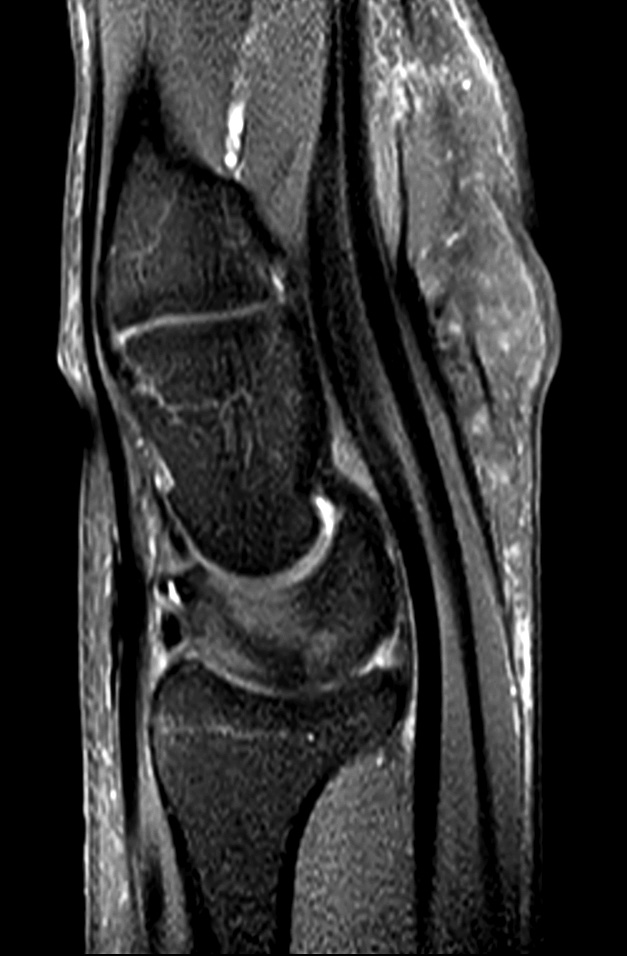

Comprehensive wrist imaging